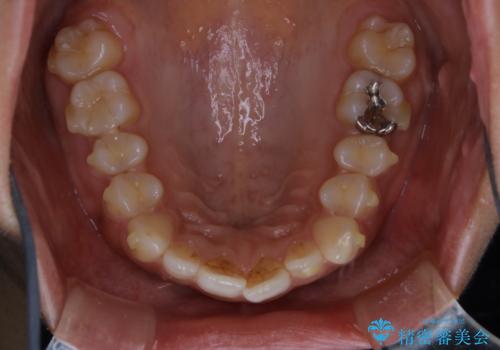

- インビザラインでの矯正治療中に、着色や汚れが気になるとのことでした。PMTC60分コースを行いました。

インビザライン治療中には、歯の表面にアタッチメント(効率的に歯の移動をするもの)を設定します。そのため歯ブラシでは届きにくい細かい部分などに、歯石や着色がついてしまうことがあります。着色などを放置していると、着色なのか、虫歯なのかの判別もしずらく正確にお口の中の状態を診断できません。

矯正治療中も定期的に歯科医院にてPMTCを受けて、お口のケアを行うことをおすすめします。